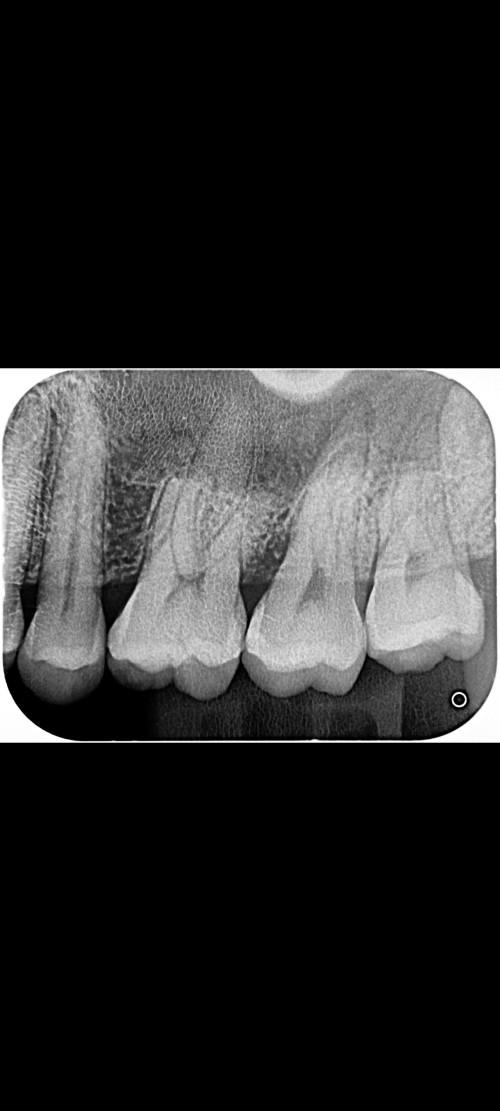

2 months ago, having intense pain, visited dental clinic and doctor said my upper left second molar is cracked/broken, but unsure how deep the crack is.

Doctor proceed with drilling some (as per picture attached) and did the filling. Was told after few days to weeks, when its totally no longer pain/sensitive then can consider to proceed with crowning.

the picture is not very clear to begin with and its no sufficient investigation for me to be sure whats going on. 2 months ago, having intense pain, visited dental clinic and doctor said my upper left second molar is cracked/broken, but unsure how deep the crack is.

Most likely i'd suggest for you to check with the dentist, do a vitality test on the tooth and take an xray to verify that it is totally fine before proceed with crowning.